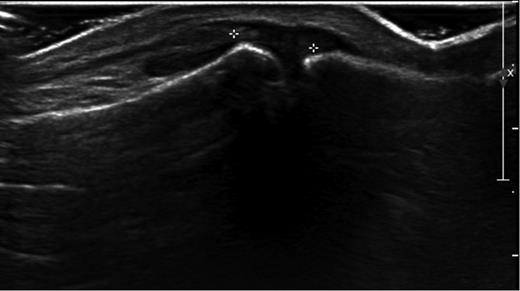

Plain radiographs showed no bony injuries, but the IPJ was subluxed in a plantar-flexed position (Fig. 1). An urgent ultrasound scan confirmed a full thickness rupture of the extensor hallucis longus (EHL) tendon at its insertion into the distal phalanx and evidence of a healing tear to the dorsal joint capsule (Fig. 2).

Ultrasound image showing ruptured IPJ capsule and avulsed EHL tendon.